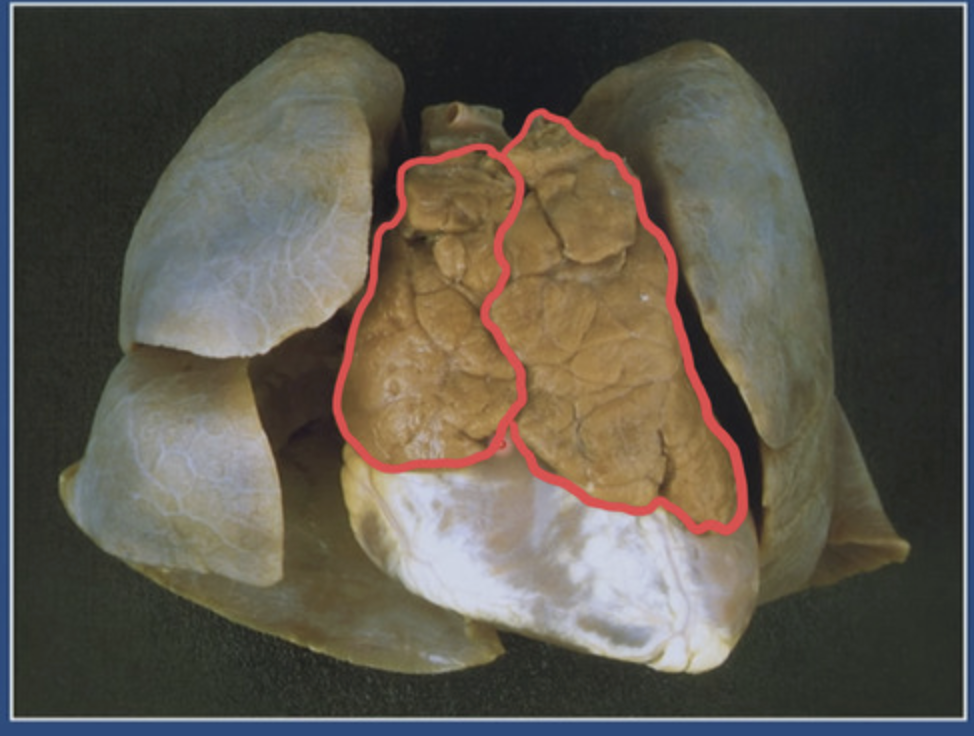

Où se trouve le thymus et quelle est sa fonction?

Le thymus se trouve derrière le manubrium sternal et devant la veine brachiocéphalique G

→ Rôle = séléction des lymphocytes T (90% éliminé)

Quelle est la destinée dans le corps à terme du Thymus?

Atrophie physiologique (= involution après la puberté)

Une fois que le thymus aura subi l’involution, que va-t-il former (progressivement)?

Il va former le tissu adipeux rétrosternal

⚠︎ Lymphopoïèse se poursuit tout au long de la vie adulte (pool de lymphocytes T formées avant l’involution et persistent)

V/F: Le thymus est bi-lobé

Vrai on peut observer 2 lobes

⚠︎ en bas âge uniquement